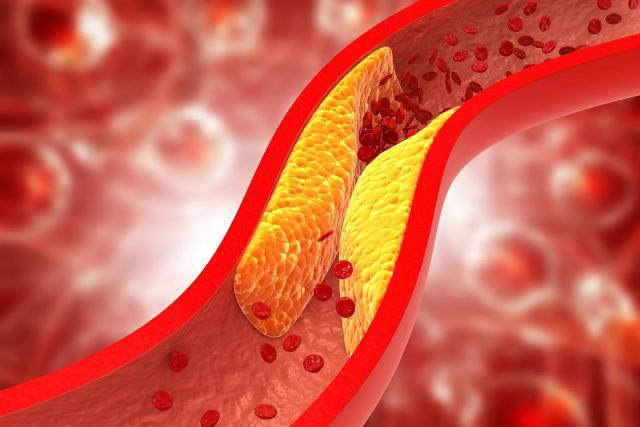

- ذكرى رحيله ..سرعلاقة فنجان القهوة بإصابة حسن فايق بالشلل النصفي